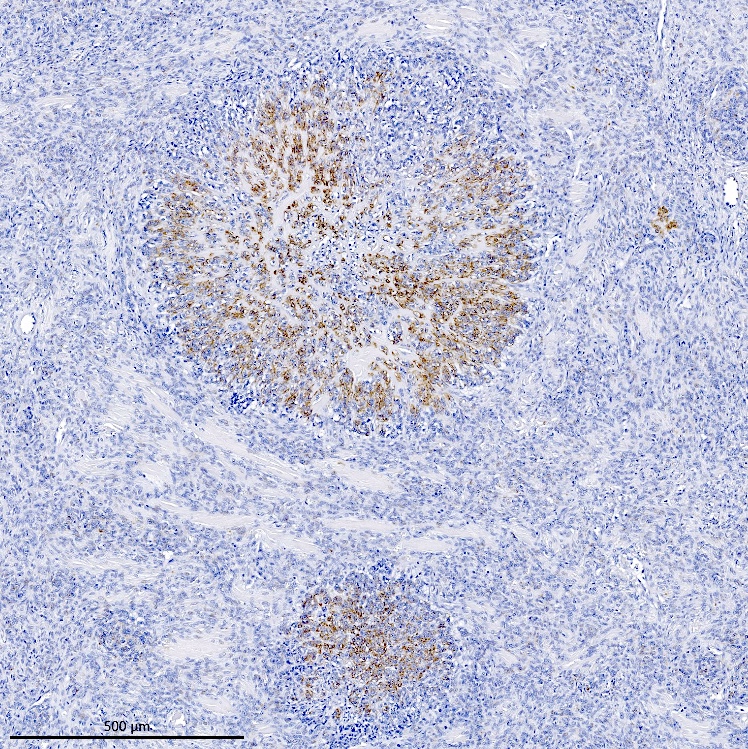

Microscopic (histologic) description

- Irregular cellular islands, forming permeative tongue-like pattern of myometrial invasion with frequent vascular invasion

- Monotonous oval to spindle cells with minimal cytologic atypia, vesicular chromatin and scant cytoplasm

- Mitotic count is usually low (< 5/10 high power fields), necrosis is usually absent

- Tumor cells may whorl around delicate arteriolar type vessels, reminiscent of proliferative phase endometrial stroma

Microscopic (histologic) images

Contributed by Elizabeth Kertowidjojo, M.D., Ph.D., M.P.H. and Ayse Ayhan, M.D., Ph.D.

Positive stains

- CD10: sensitivity 91%, specificity 45% (Int J Gynecol Pathol 2018;37:372)

D. Low grade endometrial stromal sarcoma. The tumor shows a polypoid component, as well as a characteristic permeative tongue-like invasion pattern seen on low power. The presence of invasion rules out an endometrial stromal nodule (answer B) and cellular leiomyoma (answer A). The lack of any glandular component rules out endometrioid carcinoma (answer C). While low grade endometrial stromal sarcoma can have sex cord-like differentiation, the presence of conventional low grade endometrial stromal sarcoma rules out uterine tumor resembling ovarian sex cord tumor (answer E).